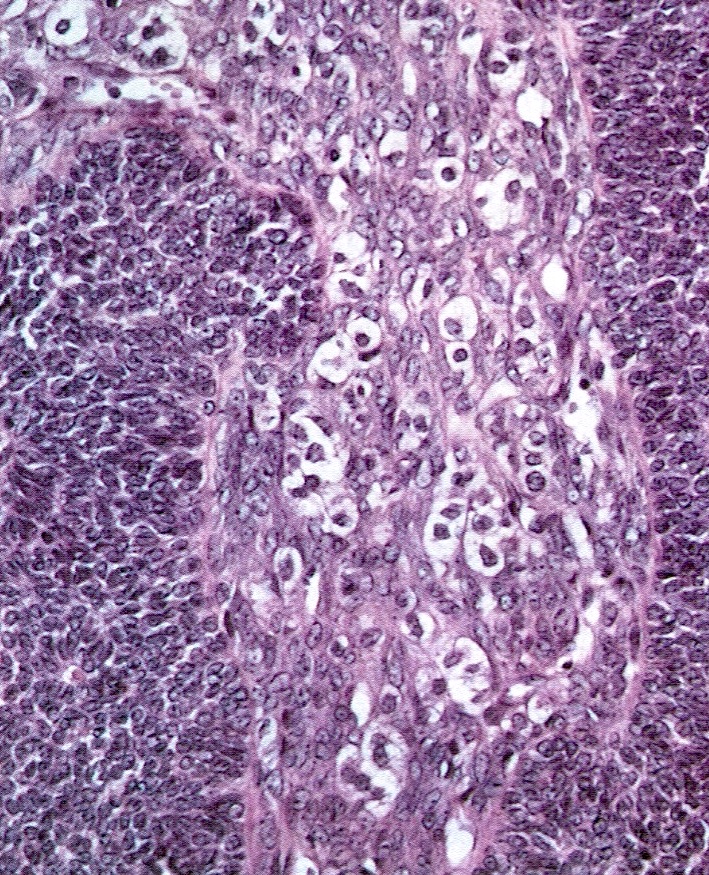

- Small, bland, cuboidal to polygonal cells with scant cytoplasm and pale, uniform angulated and usually grooved nuclei (coffee bean)

- Various patterns, including diffuse (the most common), trabecular and corded, insular, microfollicular (resembling Call-Exner bodies of the Graafian follicles: small follicle-like structures filled with eosinophilic material) and macrofollicular (the least common)

- Luteinized adult type (such as during pregnancy): rare (1%) if extensive (> 50%), plump cells with moderate to abundant eosinophilic cytoplasm, conspicuous nucleoli, no nuclear grooves, myxoid or edematous stroma; may resemble steroid cell tumor

- Rarely (2%) show focal or multifocal areas of atypical cells with enlarged hyperchromatic bizarre, some multinucleated, suggestive of degenerative change and not associated with adverse outcome (Int J Gynecol Pathol 1983;1:325)

Microscopic (histologic) images

Contributed by Shabnam Zarei, M.D. and Sharon Bihlmeyer, M.D.

AFIP images